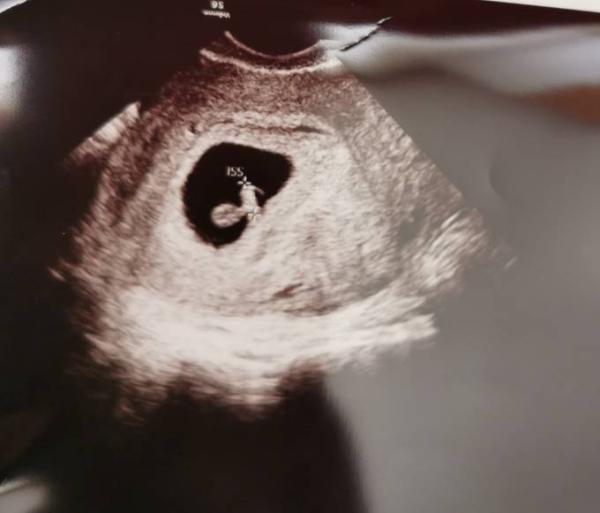

siehe Bild! Ein 5 mm kleines wĂŒrmchen

Hey dad sieht ja sehr gut aus! Ich war gestern dran und mein Foto sah exakt auch so aus, ebenfalls mit 5mm und einem kleinen Herzchen. Mich wollte der FA auch in 2,5 Wochen schon wieder sehen